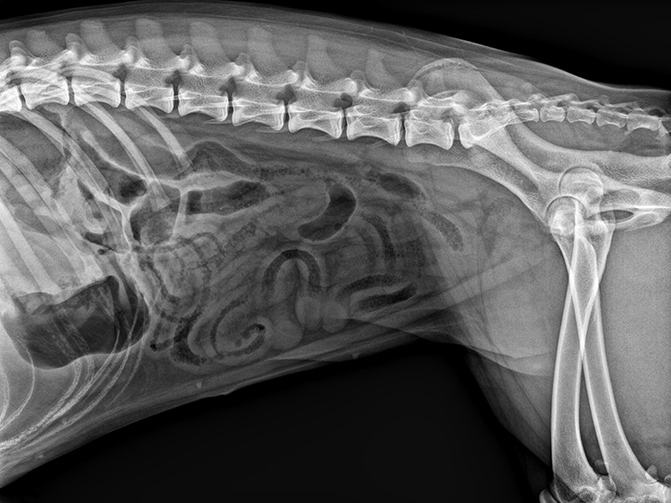

02

VET-528